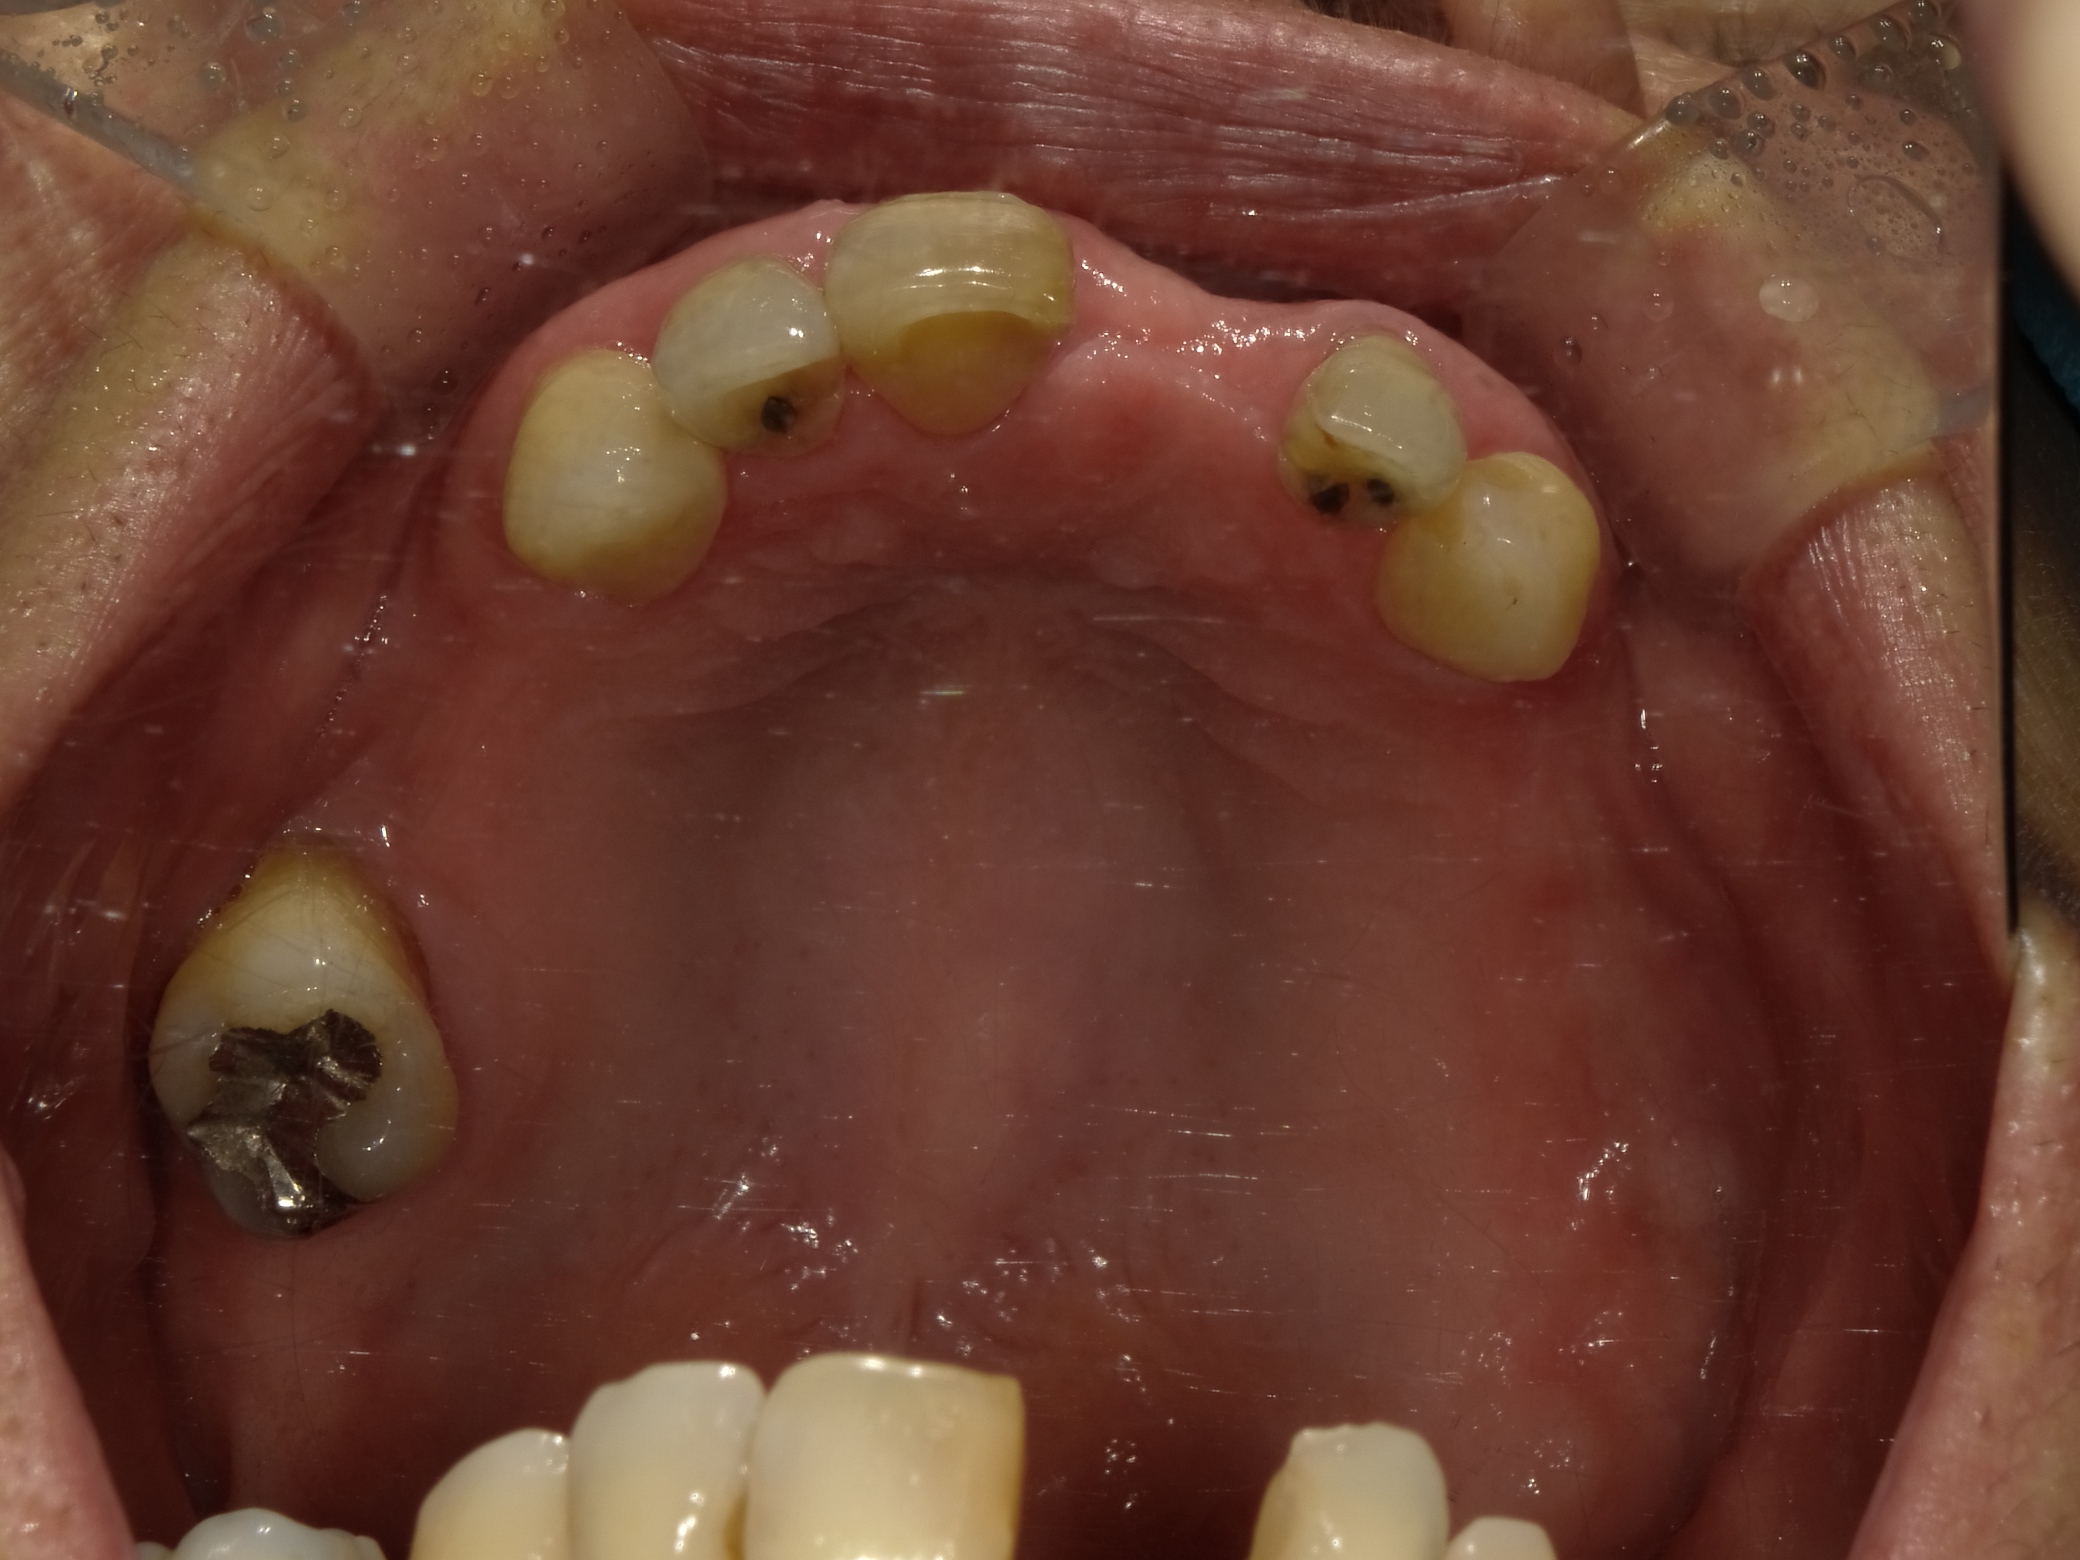

BEFORE

主訴

全体的に見た目を綺麗にしたい。奥歯でしっかり噛みたい。

診断名・主な症状

臼歯部欠損

年齢

65歳

治療内容

インプラント埋入(左下5・6,右下5・6,左上4・6)

サイナスリフト(左上4・6)

ジルコニアBr(右上6−左上3)

E –MAX CAD(右下4)

セラミックインレー(左下4)

治療期間/

約1.5年/約20回

インプラント治療 約2,000,000円

その他被せ物治療など 約1,000,000円

合計 約3,000,000円